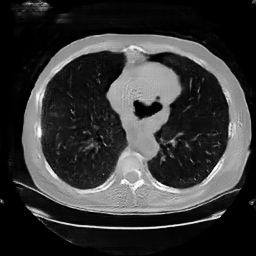

The study utilizes three 3D datasets, namely the GSP dataset[3], the LIDC-IDRI dataset[1], and the dataset employed for the Lung Nodule Analysis 2016 (LUNA16) challenge[21] which is a subset of LIDC-IDRI dataset. Samples from generated images at different stages of training are presented in Fig. 2 and Fig.3.

Figure 3: Synthetic images of CRF-GAN and HA-GAN at different iterations of training on the LUNA16 dataset